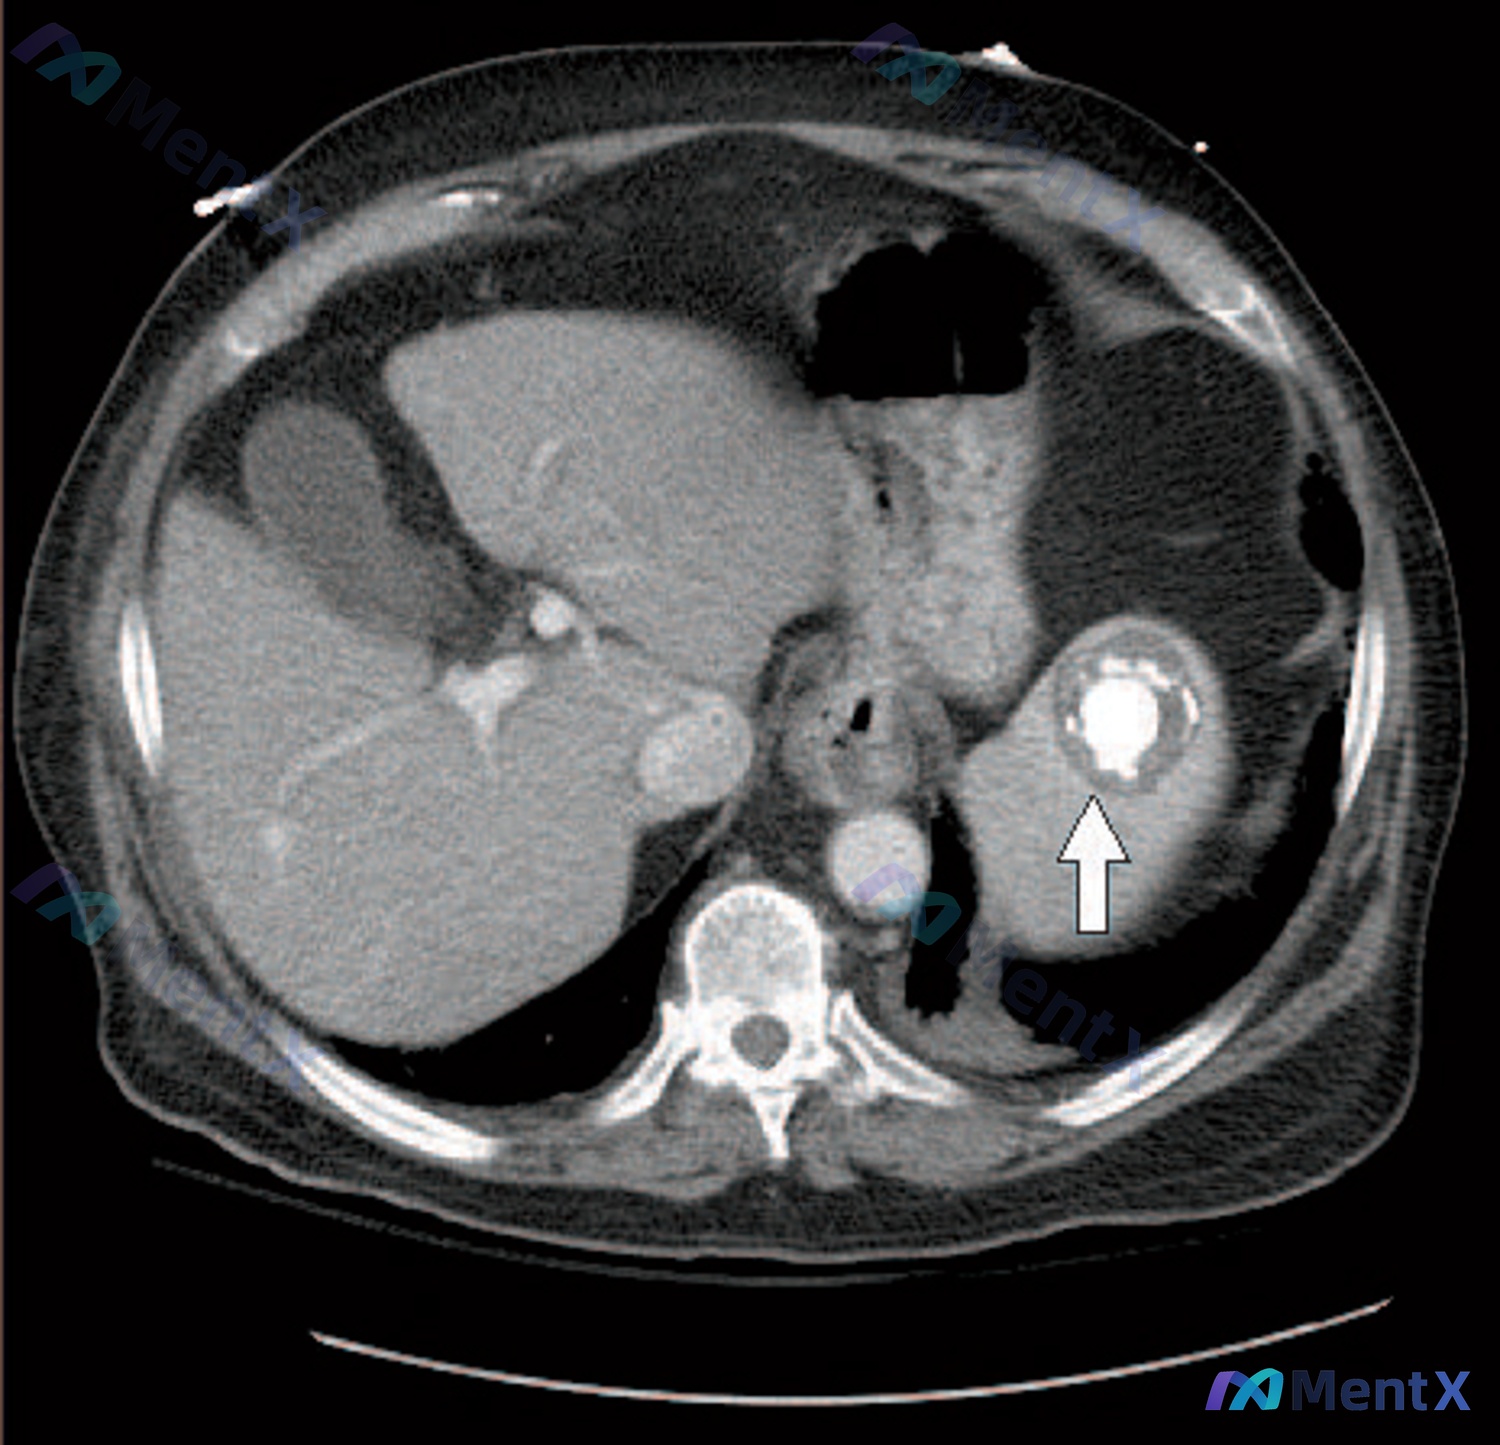

看到一份很有思辨意义的病例资料,整理了一下影像表现和分析思路,分享给大家。 病例核心信息 - 人群:男性患者 - 主诉/主要表现:全身症状(具体描述未细化,但作为核心就诊原因) - 关键影像:腹部CT平扫横断面 影像表现拆解 这张CT平扫的核心异常非常明确,在脾脏实质中部: 1. 典型形态:病灶核心...